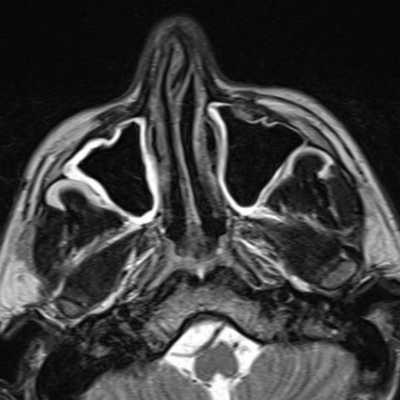

Если перед вам стоит вопрос, что лучше сделать, МРТ или КТ носа, то нужно в деталях разобраться, в чем основная разница между этими видами томографии. Для начала нужно понимать, что как при КТ пазух носа, так и при МРТ носа врач получит трехмерное изображение, но на магнитно-резонансном томографе изображения получаются за счет воздействия магнитных волн, а при компьютерной томографии на ткани идет воздействие рентгеновских лучей - то есть, облучение, причем гораздо более сильное, чем при обычном рентгене (до 10 мЗв). Однако, одно-два КТ обследования в год особого вреда здоровью человеку не принесут. МР исследование пазух носа обычно назначают при диагностике мягких тканей самих пазух и при поиске каких-то опухолей, а вот КТ лучше показывает костные ткани, особенно носовую и лицевую кость.

Классическое рентгенологическое исследование используется преимущественно для оценки лицевого скелета и придаточных пазух носа. Компьютерная томография (КТ) носа позволяет получить четкое изображение костных тканей и мягкотканных образований. Это дает возможность судить о состоянии жевательных мышц, расположенных в области крылонебной и подвисочной ямок, мышц глаза, зрительного нерва. Магнитно-резонансная томография (МРТ) носовых пазух имеет более высокое контрастное разрешение при исследовании мягкотканных образований, может быть выполнена в любой плоскости без перемены положения пациента. Она не связана с ионизирующим излучением, а магнитные поля используемой в МРТ напряженности не оказывают вредного воздействия на организм.

Диагностика заболеваний придаточных пазух носа (гайморовых, лобной, основной пазух) — сложная процедура, так как интересующие врача структуры фактически располагаются внутри лицевой части черепа и открываются в полость носа через узкие проходы. Чтобы выявить аномалии тканей, выстилающих пазухи, используется магнитно-резонансная томография. Этот метод помогает выявить патологии с меньшим риском для здоровья, чем при использовании компьютерной томографии или рентгена. Говоря о том, что показывает МРТ пазух носа, специалисты указывают, что исследование лучше покажет патологии мягких тканей, но не костей.

Обзорное обследование околоносовых пазух с использованием мощного магнитного поля проводят для выявления аномалий в строении мягких тканей. Такая особенность объясняется тем, что поле, создаваемое томографом, приводит к резонансу атомов водорода. Они в большом количестве содержатся в слизистых оболочках в придаточных пазухах и других органах, паренхиме и стенках внутренних органов, мягких тканях, сосудах и т. д. А вот костные структуры содержат мало водорода, и потому остаются почти невидимыми на снимках.